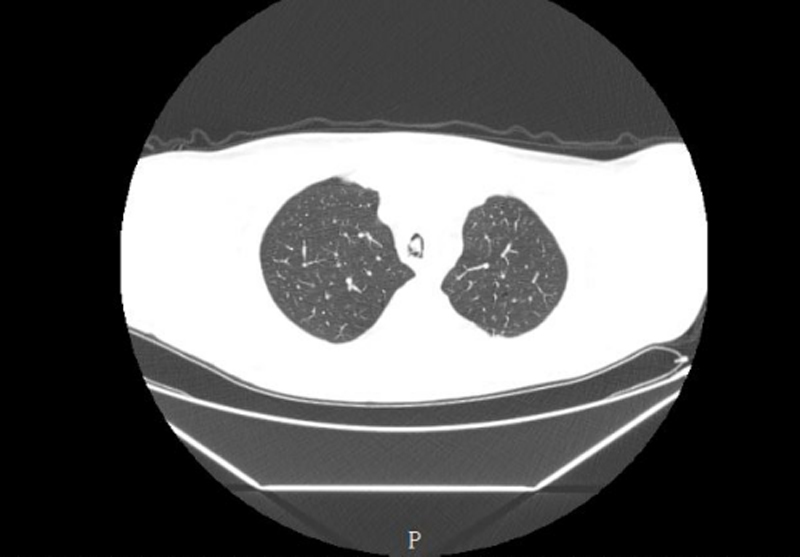

该患者因喉癌接受气管切开术后一月,于放疗期间突发气促、呼吸困难,在外院治疗症状无改善,且气促进行性加重,遂转至我院就诊。急诊胸部CT提示气管内异物可能,患者血氧饱和度持续波动,随时可能因气道阻塞引发窒息、严重呼吸衰竭或肺部感染,生命危在旦夕。由于患者气道结构特殊,异物嵌顿位置深,周围黏膜充血肿胀,手术不仅要求极高的操作精度,还需全程维持患者通气安全,难度与风险远超常规异物取出术。